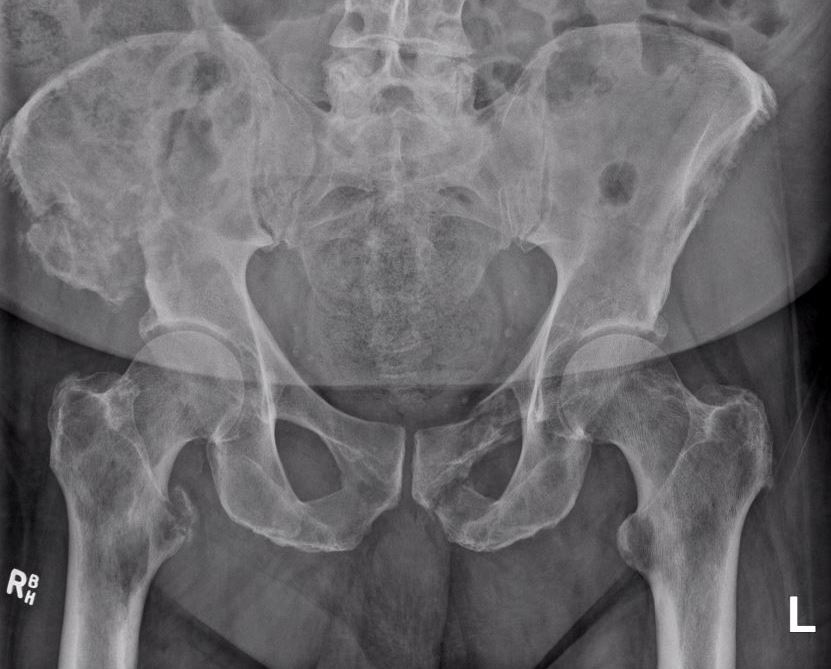

X-ray

1. Punched out lytic lesions

- axial and appendical skeleton

- widely disseminated

- soap bubble appearance

- no sclerotic reaction

2. Diffuse osteopenia

- in 15% to 25% of patients, no discrete lysis occurs

- diffuse osteopenia and osteoporosis are the only skeletal manifestations

Common in skull, ribs, sternum and pelvis